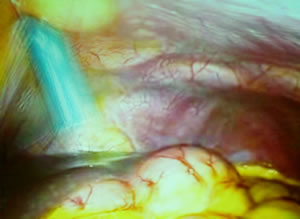

После того, как был оттеснен нисходящий отдел толстого

кишечника Константин Викторович начал рассекать париетальную

брюшину по переходной складке между левой боковой стенкой

живота и нисходящим отделом толстого кишечника. Кончиками

ножниц, на которые подан режущий ток, он притрагивался к

нежной брюшине и она сама раскрывала доступ в паранефральную

клетчатку, к сосудистой ножке почке.